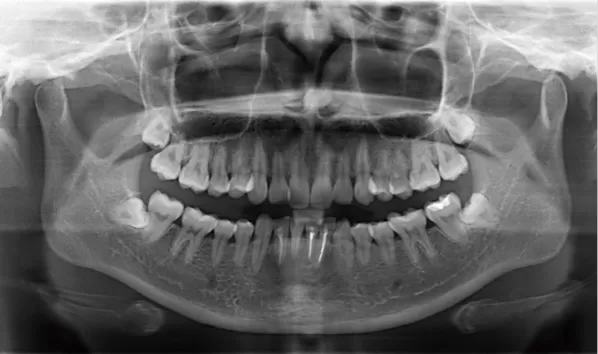

Rayons X avant le traitement

[Radiographie panoramique/Céphalogramme latéral]